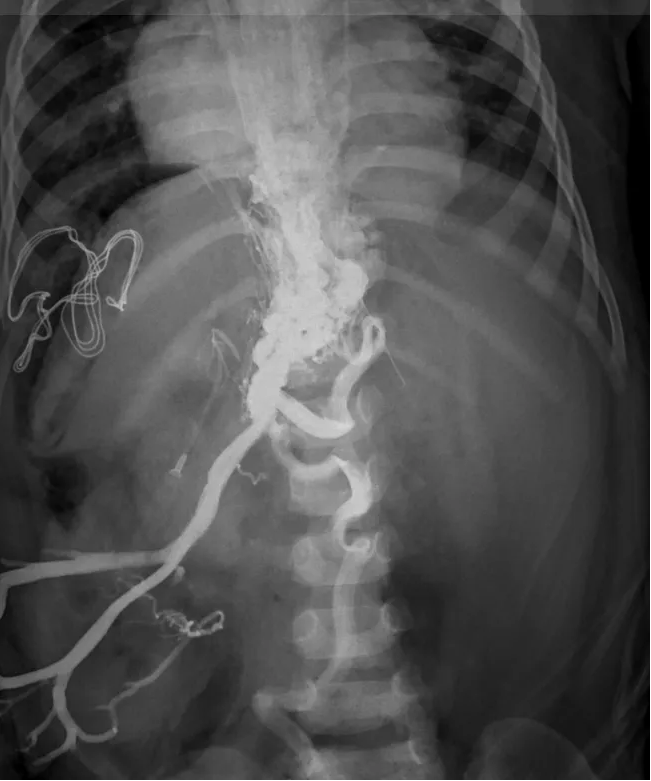

近日,佳佳转诊到首都儿童医学中心血管瘤及介入血管中心,主任申刚通过介入下肝内外门静脉造影,明确了I型 Abernethy 畸形的诊断。考虑到佳佳严重的上消化道出血及脾大脾亢等门静脉高压症状,普通外科副主任张金山会诊后,建议接受分流手术治疗,降低门静脉压力,缓解门静脉高压症状。随后,佳佳被转入普通外科接受手术治疗。

介入下门静脉造影显示门体分流,肝内外门静脉未显影